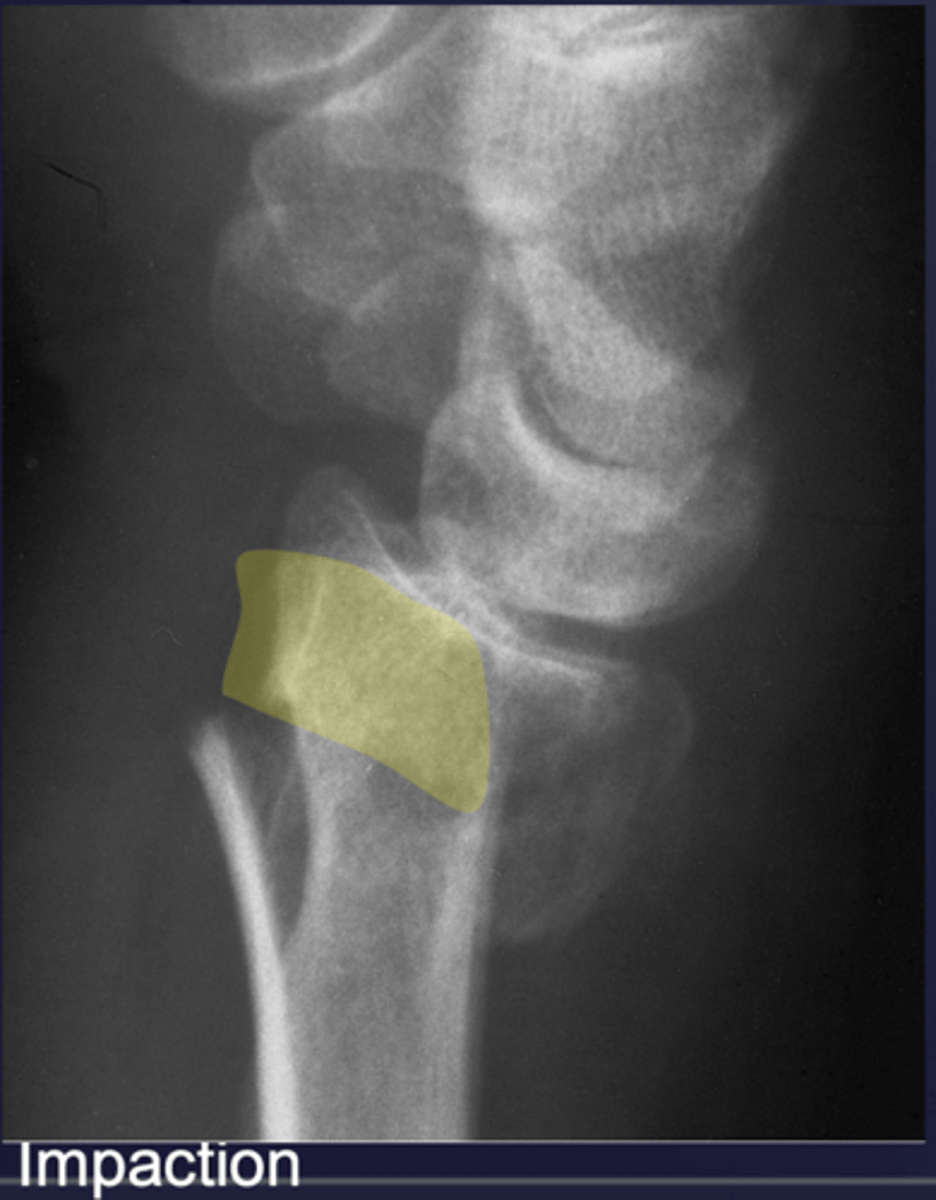

________: one fragment forced into another

Impaction (ex: compression fractures, endplate impacted; CT can help define location and the extent)